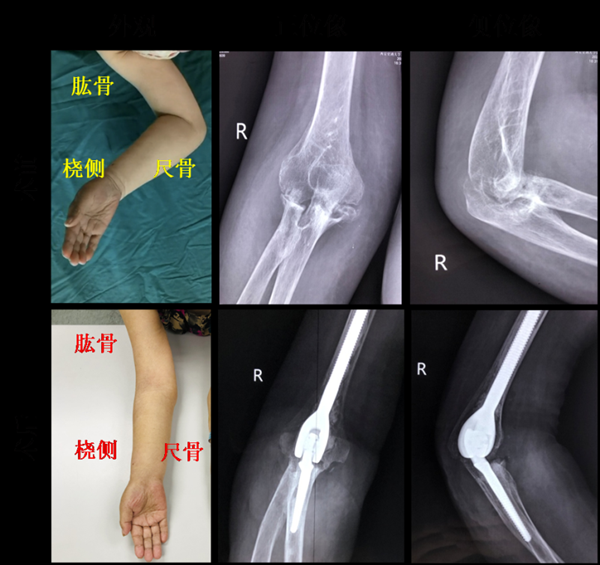

在3個月前患者的症狀更加嚴重了,右肘關節疼痛伴前臂腫脹比之前有加重跡象,疼痛導致晚上睡覺都睡不著。來到我院尋求專業治療時,我們發現,患者為右利手,前臂明顯腫脹,肘關節已經僵硬,呈畸形狀態,肘關節內側面板無破損紅腫,雙腕、雙手指關節輕度腫脹。針對患者的這些症狀,和家屬溝通後,我們建議患者入院治療,治療前安排給患者的雙手、雙腕、雙肘關節都進行了B超,從結果來看:患者雙側肘關節滑膜明顯增厚,肘關節骨質破壞;雙腕皮下軟組織增厚、水腫,雙側腕關節滑膜增厚,類風溼系列回報:抗環瓜氨酸抗體陽性,結核感染系列陰性。

結合病人病史、查體及一系列輔助檢查,先排除感染性肘關節疾病及夏科氏關節病,我們的診斷結果考慮為:類風溼性關節炎導致的終末期肘關節骨質破壞,伴骨質疏鬆。

我們把診斷結果同患者和家屬進行了溝通,對於類風溼性關節炎末期的症狀,我們的建議是:進行右肘關節整體置換,因為單純的吃藥或是理療,已經不能解決問題了,有必要透過手術的方式來解決病痛。當然這個手術本身難度係數較大,再加上患者年齡偏大,幸好患者沒有什麼嚴重的心血管疾病,我們與家屬進行了充分溝通,經家屬同意後,最終進行了手術。

經過我們不斷的影像重建,研究方案,我們決定迎難而上,個性化定製了國產鉸鏈式人工肱尺關節假體。在主任的全程跟蹤指導下,我們在對患者進行全麻後進行了手術,施行右側肘關節全部置換術(totalelbowarthroplasty,TEA)。這個手術的難點在於:患者的肘關節解剖時結構破壞嚴重,炎症導致的病變又位於肘窩附近,那裡重要的血管和神經密佈,術中要準確切除破壞骨質,重建肘關節結構,才能恢復肘關節功能。這對我們也是一個挑戰。

經過1個半小時的配合和奮戰,我們終於完整切除滑膜及破壞的骨質,並重建肱尺關節。病人在整個手術過程中,身體狀況都很正常,沒有出現任何不適現象,手術結束後,我們對患者進行了病理檢查。

患者根據醫囑,規律口服艾拉莫德,控制活動性類風溼性關節炎3周,輔助系統的功能訓練及專業的康復指導,右前臂腫脹明顯消退、肘關節活動度極大改善。比來院時的狀態好多了,手臂的活動也順暢了很多。患者及家屬很滿意,出院回家。